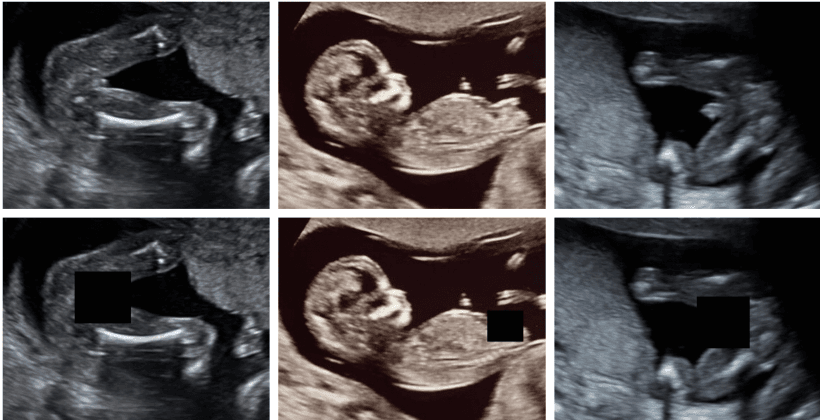

Fetal Gender Masking

Deep learning approach for automatically masking fetal gender indicators in ultrasound imagery to support blind studies. Uses segmentation networks trained on medical imaging data to ensure privacy compliance in prenatal research.